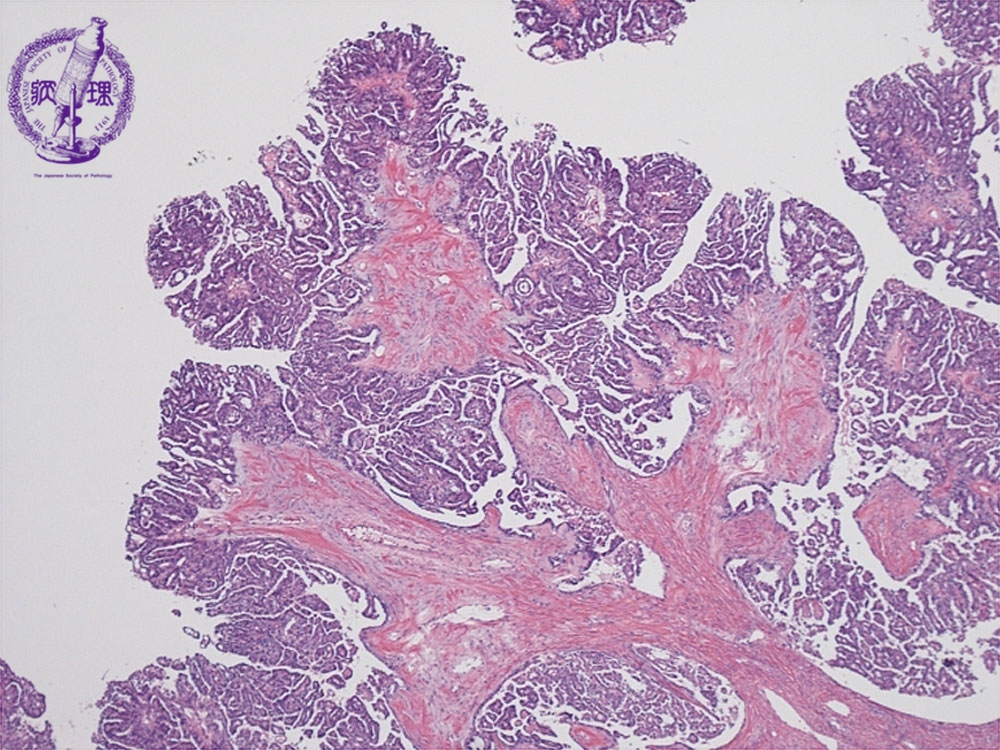

卵巣漿液性嚢胞腺癌ミクロ像(HE弱拡大)

ミクロ像(HE弱拡大):卵巣漿液性嚢胞腺癌。比較的小型で立方状の癌細胞が線維性の間質(黄色点線)を伴いながら乳頭状に増殖している。